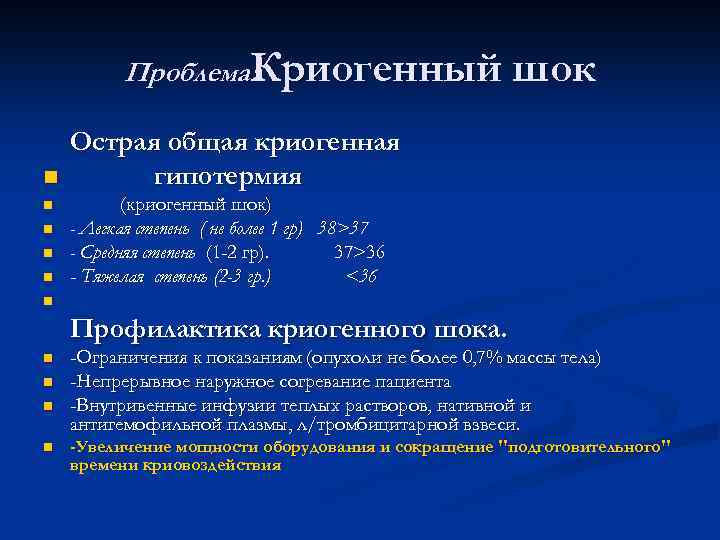

Проблема: Криогенный n n n шок Острая общая криогенная гипотермия (криогенный шок) - Легкая степень ( не более 1 гр) 38>37 - Средняя степень (1 -2 гр). 37>36 - Тяжелая степень (2 -3 гр. ) <36 n Профилактика криогенного шока. n n -Ограничения к показаниям (опухоли не более 0, 7% массы тела) -Непрерывное наружное согревание пациента -Внутривенные инфузии теплых растворов, нативной и антигемофильной плазмы, л/тромбицитарной взвеси. -Увеличение мощности оборудования и сокращение "подготовительного" времени криовоздействия

Проблема: Криогенный n n n шок Острая общая криогенная гипотермия (криогенный шок) - Легкая степень ( не более 1 гр) 38>37 - Средняя степень (1 -2 гр). 37>36 - Тяжелая степень (2 -3 гр. ) <36 n Профилактика криогенного шока. n n -Ограничения к показаниям (опухоли не более 0, 7% массы тела) -Непрерывное наружное согревание пациента -Внутривенные инфузии теплых растворов, нативной и антигемофильной плазмы, л/тромбицитарной взвеси. -Увеличение мощности оборудования и сокращение "подготовительного" времени криовоздействия